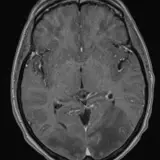

Over 2,100 interactive radiology cases, curated by radiologists for your level of training. Scroll, window, and view cases full screen — just like on PACS. Click linked findings in each writeup to jump straight to them on the image. Cases include sample reports, a focused discussion section, original illustrations, and videos.

Casos totalmente interactivos con las herramientas que esperaría de un PACS: scroll, ventana, zoom, pan, mediciones, ROI y modo de pantalla completa.

• Anotaciones enlazadas

Anotaciones extensas resaltan los hallazgos clave directamente sobre los casos. Haga clic en los hallazgos enlazados dentro de la descripción del caso para saltar a su ubicación exacta en el estudio.

Aprenda con eficiencia gracias a hallazgos de imagen anotados e ilustraciones